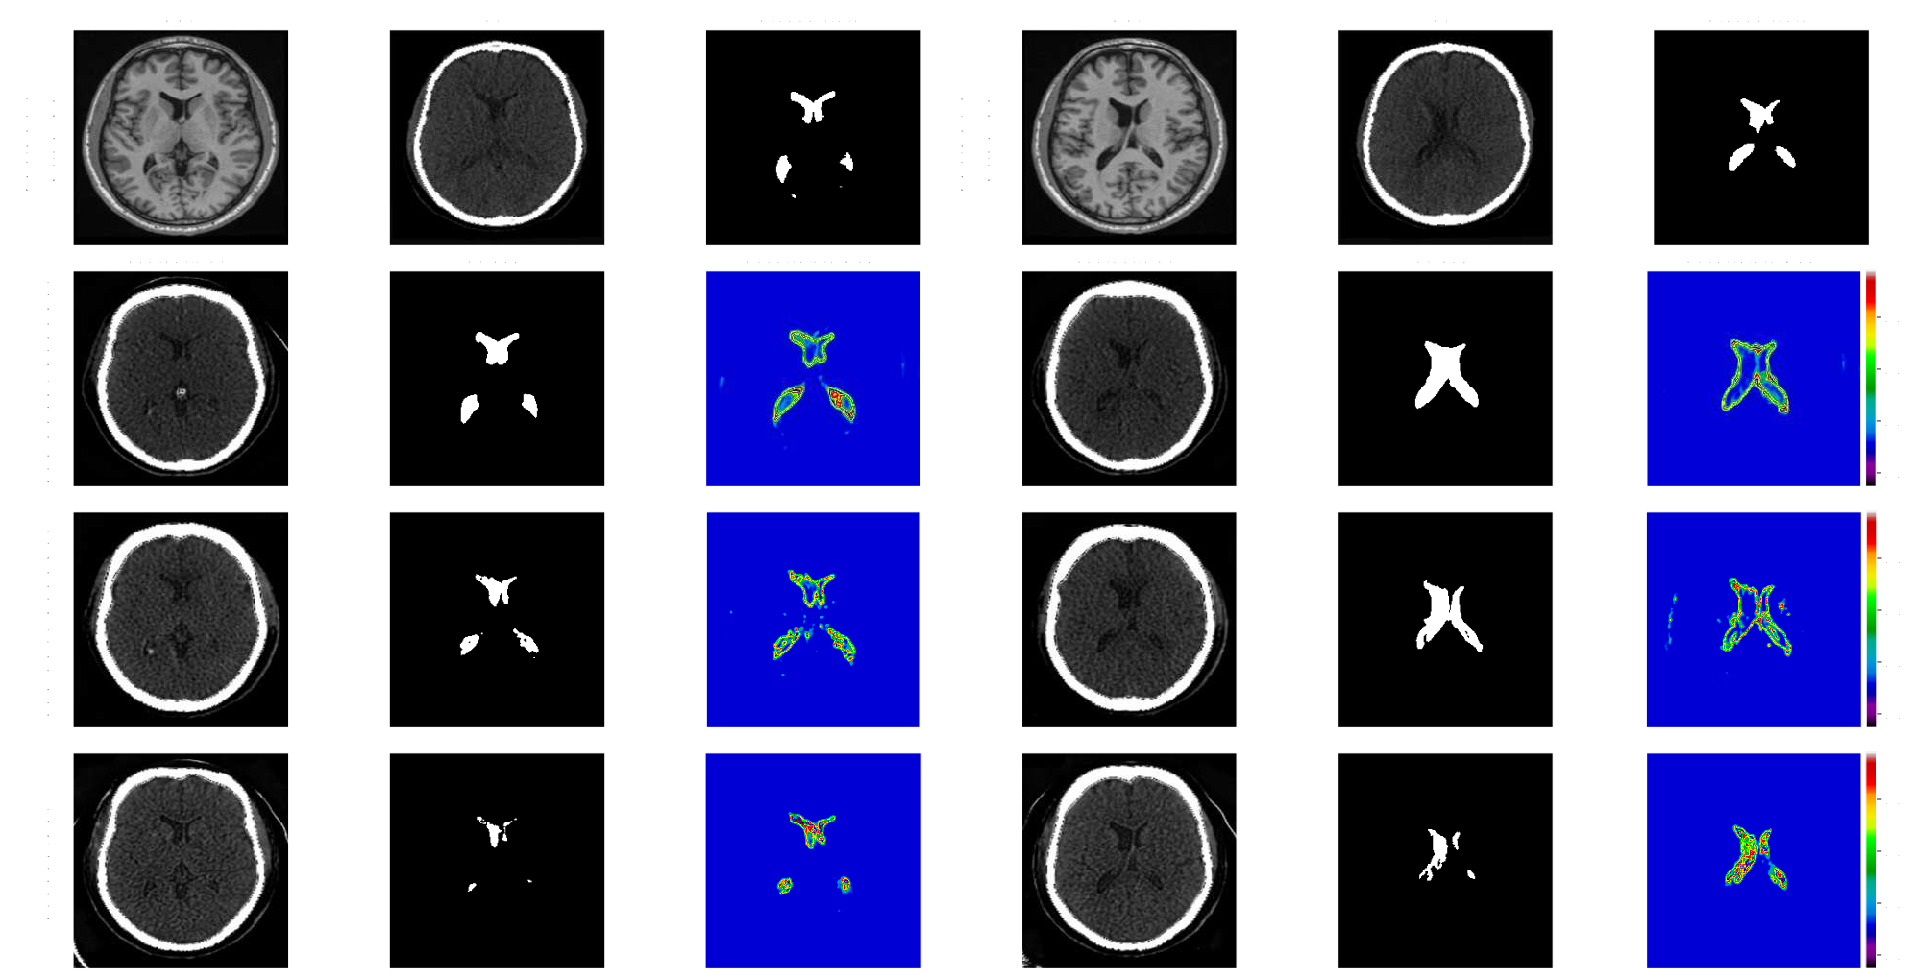

Quantitative segmentation and image translation evaluations across models are shown in Table 1, with qualitative comparisons in Fig. 3. Overall, our proposed method (E2E-UNSB+R2AUNet), which achieved a Dice score of 0.78±0.27, an IoU of 0.70±0.29, and a 3D Dice score of 0.73±0.08, significantly outperformed the other segmentation models(p<<<0.05). The UNSB model demonstrated a clear advantage over the end-to-end approaches (E2E-UNSB+R2AUNet, E2E-CUT+R2AUNet, and SynSeg-Net). When comparing the “end-to-end” and “two-stage” approaches with “UNSB vs. CUT” and “R2AUNet vs. UNet” settings, we observed better segmentation accuracy (p<<<0.05) for the end-to-end models while the two-stage models have a slight edge in terms of the quality of MRI-to-CT translation. In the segmentation module, the R2AUNet was compared against the vanilla UNet in both “end-to-end” and “two-stage” approaches, and the first consistently provided superior outcomes. Noticeably, between E2E-UNSB+R2AUNet and E2E-UNSB+UNet, the 2D Dice score, IoU and 3D Dice score were increased by 5%, 4%, and 6%, respectively by the R2AUNet. Finally, although performing CT-to-MRI translation is an alternative method to achieve ventricle segmentation, it significantly reduced the segmentation performance, with heavier impacts on models based on CUT. To validate segmentation uncertainty, we correlated DSC with uncertainties across all test slices. E2E-UNSB+R2AUNet showed a stronger correlation (-0.86) compared to E2E-CUT+R2AUNet and SynSeg-Net (-0.81 and -0.41, respectively).

Refer to caption

Figure 3: Qualitative demonstration of ventricle segmentation and uncertainty measures for two subjects with two different slices using different end-to-end methods.